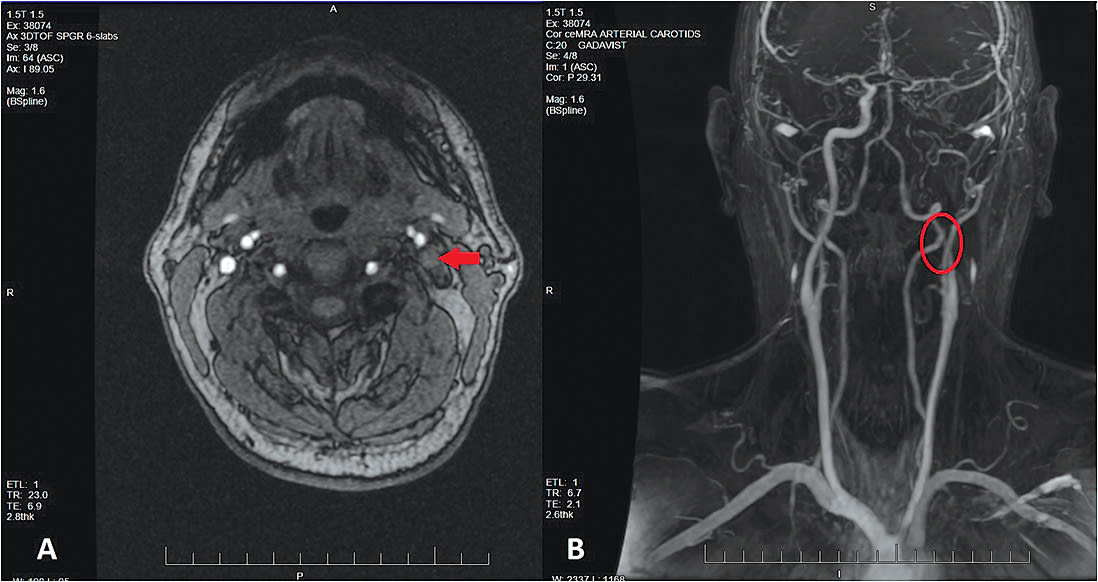

MRA imaging showed complete occlusive internal carotid artery dissection at the level of the petrous region (Figure 1). Thankfully, the patient had patent and healthy anterior cerebellar and posterior communicating artery collaterals to compensate for the reduced blood supply.